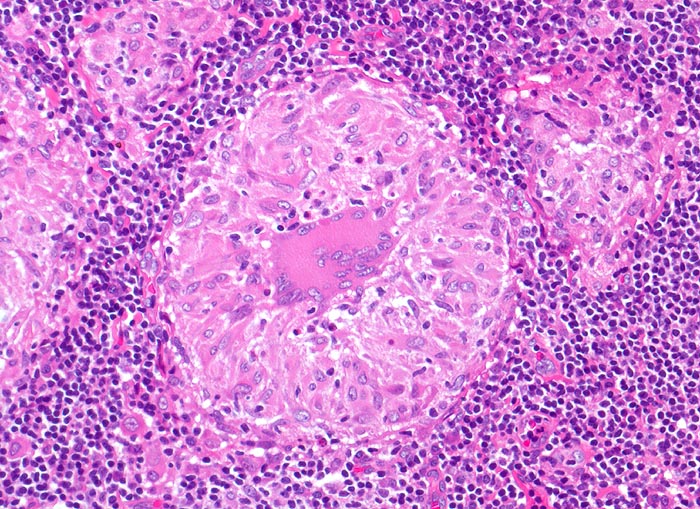

Lymphknotensarkoidose (Morbus Boeck)

Lymphknoten, inguinal

In der Bildmitte ein rein produktives Granulom mit zentral gelegener Riesenzelle vom Langhanstyp und Epitheloidzellen (längsovale, schuhsohlenartige Kerne und reichlich Zytoplasma).

Vergrösserte inguinale Lymphknoten bei bekannter Sarkoidose mit Befall der Lungen.

Epitheloidzellige Granulome sind nicht spezifisch für Sarkoidose. Sie können beispielsweise bei guter Abwehrlage auch bei einer Tuberkulose auftreten. Seltenerweise kann man auch bei einer Sarkoidose verkäsende Granulome nachweisen. Die Diagnose einer Sarkoidose sollte erst nach Ausschluss anderer granulomatöser Entzündungen gestellt werden. Zum histologischen Ausschluss einer rein produktiven Tuberkulose wäre es notwendig, eine Ziehl-Neelsen-Färbung durchzuführen, um die säurefesten stäbchenförmigen Tuberkelbakterien nachzuweisen. Diese Bakterien wären in den Epitheloidzellen und vor allem auch in den Riesenzellen zu finden. Bei relativ guter Abwehrlage können die säurefesten Stäbchen aber auch bei der Tuberkulose fehlen.